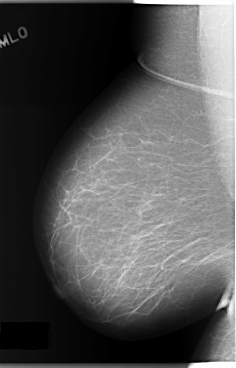

C_0132_1.RIGHT_CC

RIGHT_CC LINES 5888 PIXELS_PER_LINE 3512 BITS_PER_PIXEL 12 RESOLUTION 50 NON_OVERLAY